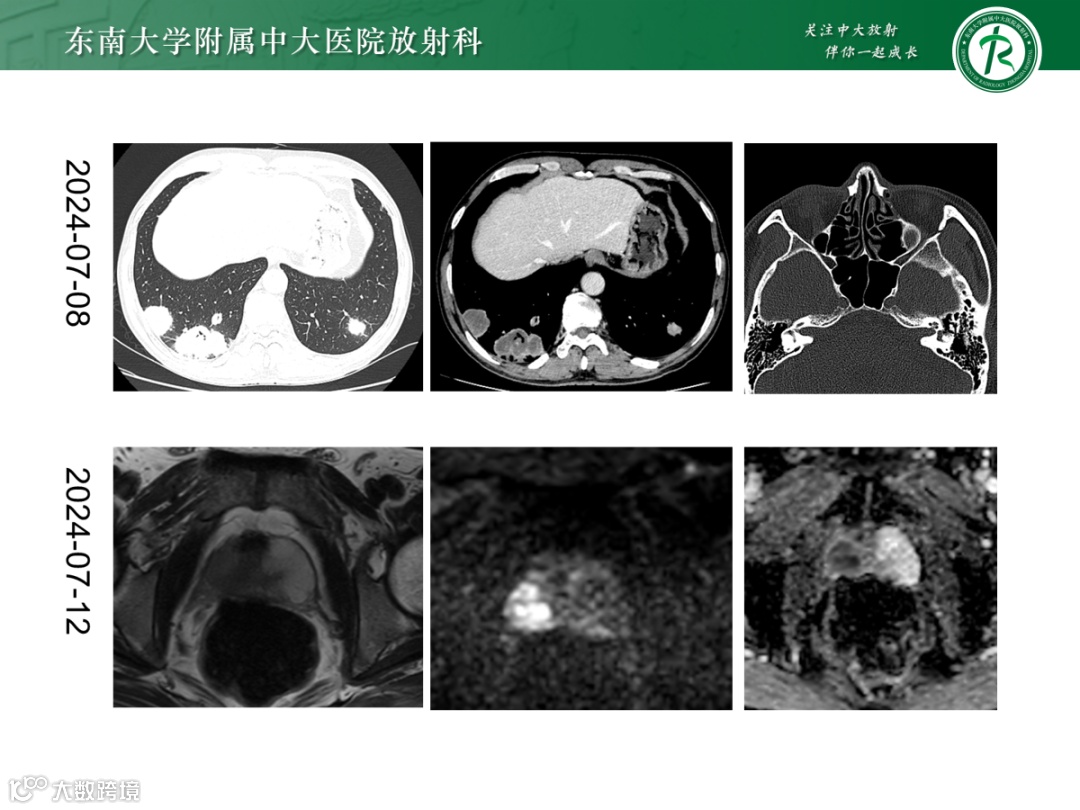

影像学表现